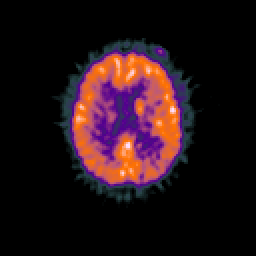

Glioma overlay -- Slice #72